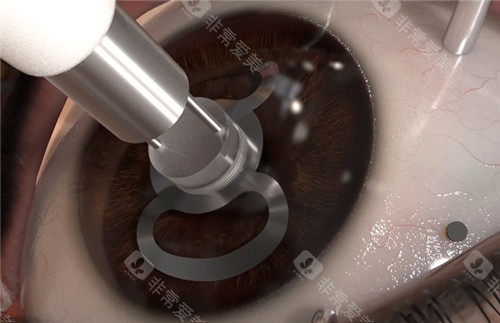

含金量:飞秒激光辅助切口(精度0.1mm),术后散光降低40%

黑科技:3mm微切口植入,无需缝合,术后次日可视物,适合大泡性角膜病变

飞秒激光辅助比传统手术贵30%-50%,但精密度更高、改善更快

飞秒激光移植系统实现微米级切割,供体利用率提升40%